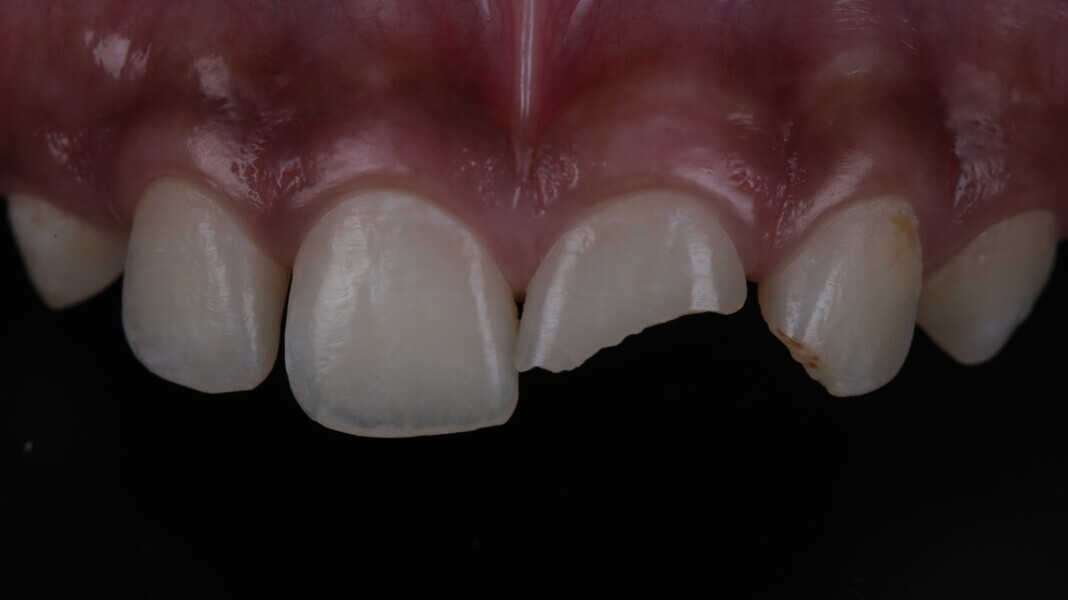

A 10-year-old male patient reported with a complaint of trauma to the upper left central and lateral incisors, involving the enamel and dentin. Direct composite was used in multi-layers and the smile was restored. This article explains detailed steps in the polychromatic layering technique with special emphasis on the finishing and polishing protocol. 3M Espe Filtex Z350 Xt was used with a universal bonding agent.

Fig 31-41: Polishing protocol and post-op

The article demonstrates how using the right protocols and armamentarium for composite materials can give life-like results in a short time in a minimally invasive way. No single layering technique can ensure a 100% success rate. Regardless of the technique, establishing good secondary and tertiary anatomy and thorough polishing are the key steps that make a restoration look more natural. Composite is the perfect material for allowing correction of mistakes or improvement.